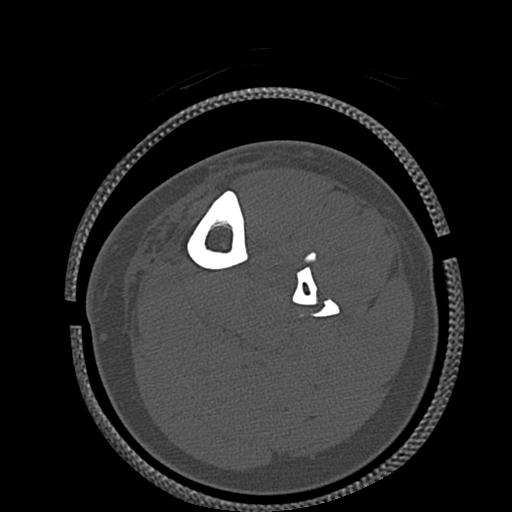

56476 8/28 4R 1/21 2R 左足関節 デジカメ写真 72歳女性 右足関節AS